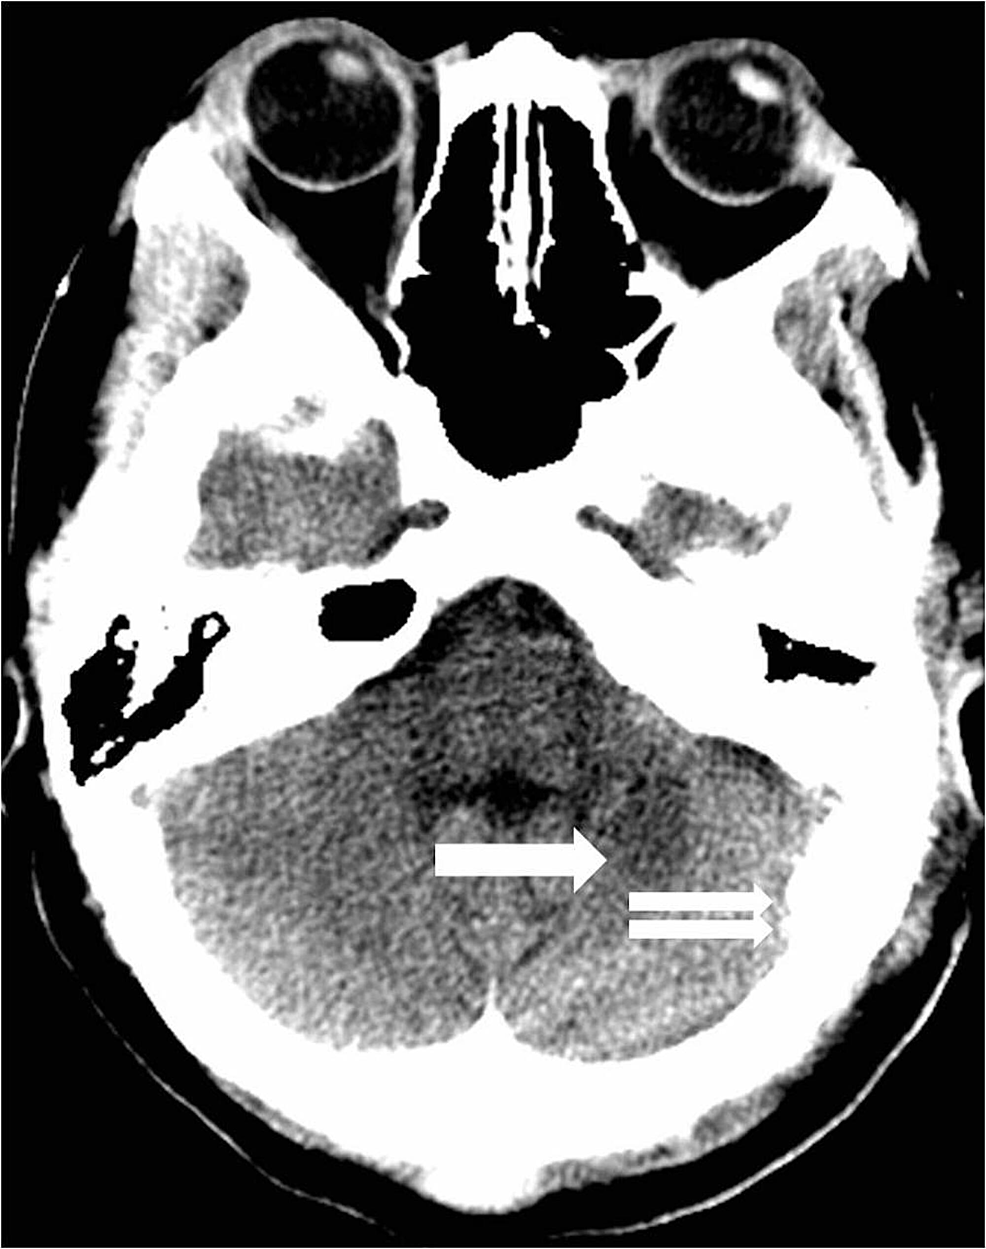

A 39-year-old female with a history of posterior fossa AVM, AIDS, and hypertension presented with headaches, dizziness, blurry vision, and left-sided facial numbness. She had a previous history of hemorrhage from an AVM in the posterior fossa which was treated with a partial embolization two years prior. She was scheduled for a resection of the AVM at that time but was lost to follow up. Physical exam showed no abnormalities on admission. CT scan of the head showed an acute parenchymal hemorrhage in the inferior left cerebellum (Figure 6).

CT angiogram (CTA) showed a left posterior fossa vascular malformation that had remained largely unchanged from the prior admission two years earlier (Figure 7).